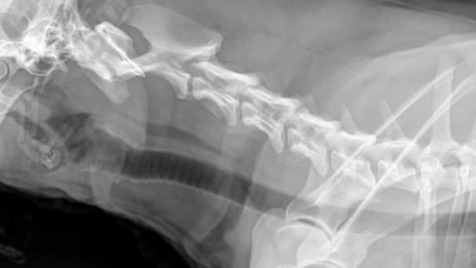

Witam jestem właścicielem suczki o imieniu "Kora". Zbieram pieniądze na operacje dla niej, ponieważ dzisiaj rano (29.01.22) Suczka została potrącona przez samochód i przez to ma problem z kręgosłupem i płucami. Koszt operacji to 4,5 Tysiąca złotych. Piesek ma 3 lata i jest nam bliski, ma jeszcze dużo życia przed sobą... Każda złotówka się liczy. Zdjęcie poniżej. + 1,500 Pobyt w klinice 3 doby.